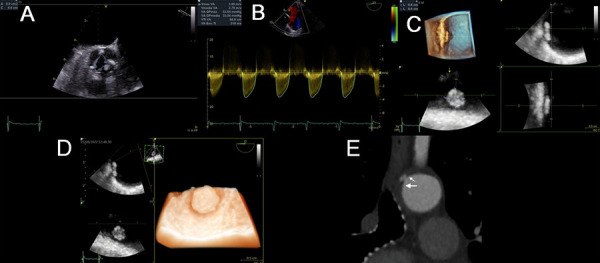

Aortic stenosis is associated with aortic plaques in up to 85% of cases because they share risk factors and pathogenic pathways. Intrinsically, complex aortic plaques carry a high risk of stroke, which has also been demonstrated in the context of aortic stenosis, especially in patients who underwent percutaneous or surgical replacement. Transesophageal echocardiography (TEE) is the imaging test of choice to detect plaques in the thoracic aorta and classify them as complex plaques. Furthermore, the 3D modality allows us to better specify its dimensions and anatomical characteristics, such as added thrombi or the presence of ulcers inside. This review aims to evaluate the use of TEE to detect complex aortic plaques in patients with an indication for percutaneous or surgical aortic valve replacement. To highlight the association between aortic stenosis and complex aortic plaques, we attached to the review some TEE studies from our experience.